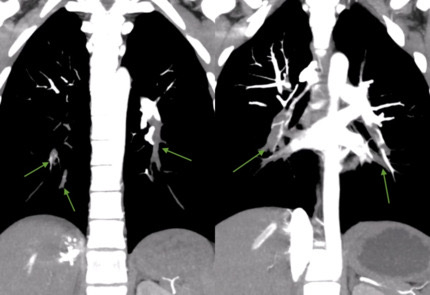

An 18-year-old female presented to the emergency department with acute-onset dyspnea, chest pain, nausea, vomiting, and syncope after four months of oral contraceptive use and active vaping. Physical examination revealed tachycardia (135 bpm) and tachypnea, with ECG showing sinus tachycardia. Laboratory studies demonstrated dramatically elevated D-dimer (12,756), elevated proBNP (660), and troponin (299 225). Echocardiography revealed the D-sign [Image 1] classic McConnell sign - severely dilated right ventricle with hyperkinetic apex and hypokinetic basal-to-mid free wall [Image 2], confirming massive PE with acute cor pulmonale. CT angiography revealed extensive bilateral pulmonary emboli with signs of right heart strain [Image 3]. Immediate anticoagulation with heparin was initiated, followed by ICU admission where alteplase was administered for massive PE. Remarkably, the patient demonstrated complete heparin resistance with no APTT response despite escalating doses over 24 hours and the decision was made to switch to rivaroxaban 15mg twice daily. Patient symptoms significantly improved on day 3 and was eventually discharged with follow up appointment to hematology.